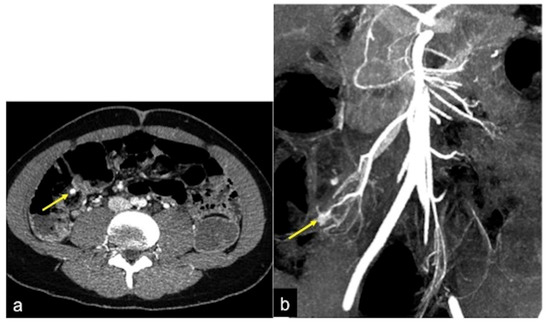

| Aorto-Enteric Fistula (Figure 31) | Bleeding in a patient with a history of surgery for aortic aneurysm. | A connection between the aorta and the intestinal lumen. Absence of adipose cleavage planes. |